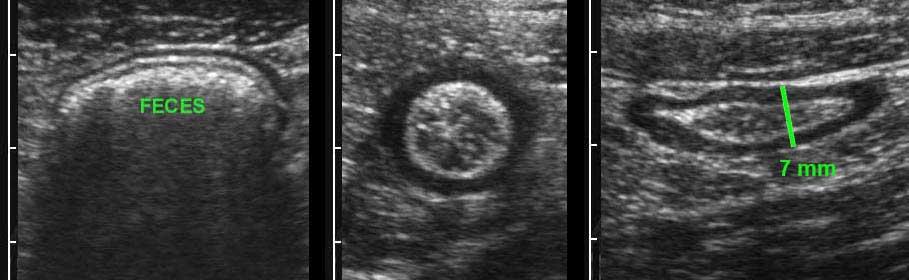

Colon

Hình ảnh dọc (trái) và ngang (phải) của đại tràng sigma rỗng ở bệnh nhân gầy.

Trong hình ảnh mặt cắt ngang, ba vùng dày lên cục bộ của lớp cơ (đầu mũi tên) đại diện cho ba dải cơ dọc kết tràng (đầu mũi tên).

Đại tràng bình thường chứa đầy phân (trái), trong quá trình co thắt (giữa) và trong quá trình giãn và nén (phải).

Normal colon wall thickness during compression is 3-4 mms.

Bóng lưng âm học của phân cản trở việc hiển thị siêu âm thành sau (bên trái).

Đại tràng được phân biệt với ruột non bởi vị trí, nội dung phân, nhu động thưa và lớp cơ ngoài dày với ba dải cơ dọc (tenia coli).

Lớp cơ của đại tràng sigma có thể thay đổi đáng kể về độ dày, chủ yếu do sự co bóp.

Sự dày lên vĩnh viễn của lớp cơ có liên quan đến sự phát triển của các túi thừa (mũi tên).

Sigmoid diverticulosis in four different patients.

Các túi thừa chứa đầy phân được quan sát rõ nhất khi đại tràng co lại.

Chúng biểu hiện là các cấu trúc phản âm sáng với bóng cản âm ở bờ ngoài của đại tràng.

Lưu ý độ dày thay đổi của lớp cơ ở bốn bệnh nhân này.